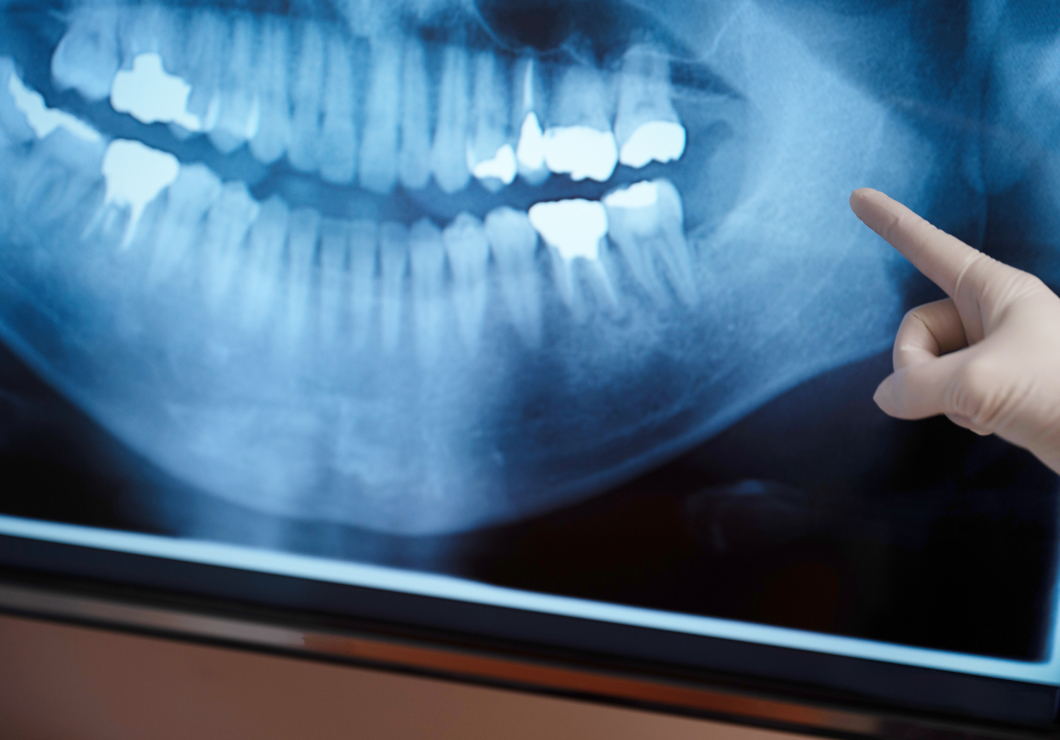

かくれたむし歯も

しっかり発見

当院では定期的に、パノラマレントゲンや「バイトウィング」という方法でレントゲン検査を行います。バイトウィングは専用のフィルムを噛んでいただき、歯を真横から水平に撮影することが特徴です。一般的なレントゲンよりも、むし歯を見逃しにくく、特に歯と歯の間のむし歯や、初期むし歯の発見に役立ちます。